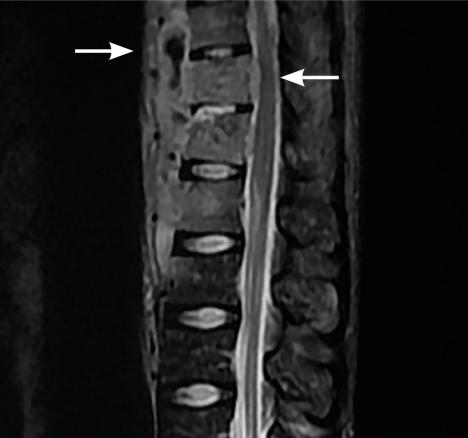

L’imagerie montrait : sur la tomodensitométrie (TDM) thoracique une miliaire tuberculeuse pulmonaire et des adénopathies médiastinales ; sur l’imagerie par résonance magnétique (IRM) du rachis une spondylodiscite T11-T12 (fig. 1 ) ; sur la TDM abdominale des abcès paravertébraux de T9 à T12 le long des psoas (fig. 2 , flèches blanches) et des lésions micronodulaires hépatiques multiples (fig. 2 , flèche jaune) ; sur l’IRM myocardique des signes de péricardite (fig. 3 , flèches). La ponction lombaire montrait une méningite. Un tuberculome était visible sur l’IRM cérébrale, entouré d’un œdème périlésionnel (fig. 4 ). Le diagnostic de tuberculose disséminée était prouvé par polymerase chain reaction sur une ponction d’abcès. Compte tenu de l’atteinte neuroméningée, un traitement adjuvant par corticothérapie s’imposait dans le cas présent, de même qu’une antibiothérapie de 9 à 12 mois.1

L’imagerie montrait : sur la tomodensitométrie (TDM) thoracique une miliaire tuberculeuse pulmonaire et des adénopathies médiastinales ; sur l’imagerie par résonance magnétique (IRM) du rachis une spondylodiscite T11-T12 (